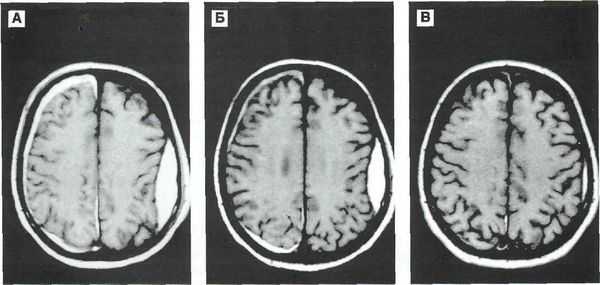

Ушибы мозга часто появляются при КТ через 12-24 часа, таким образом, данные персональной КТ головы у пациента с ушибом мозга могут быть нормальными. Единственной подсказкой к его наличию будет сниженный показатель Шкалы комы Глазго (ШКГ), когда ушибы головы выглядят как умеренная травма, но с ШКГ 9-13.

Ушибы состоят из областей пропитанной кровью ткани, в которых разрушен гематоэнцефалический барьер, что создает неоднородную зону поврежденной паренхимы мозга, перемешанной с излившейся кровью. По мере развития ушибов после повреждения, они не только становятся более заметными при КТ головы, но и могут вызвать нарастающий масс-эффект вследствие отека поврежденного мозга, кровотечения из разрушенных мелких сосудов, или сливаться, образуя зону внутричерепного кровоизлияния. Умеренные повреждения головы могут прогрессировать до тяжелых повреждений примерно в 10% случаев, а изначально небольшие ушибы и гематомы могут постепенно увеличиваться и приводить к быстрому ухудшению, даже у ранее бодрствовавших и оживленных пациентов, получивших явно нетяжелые повреждения головы.